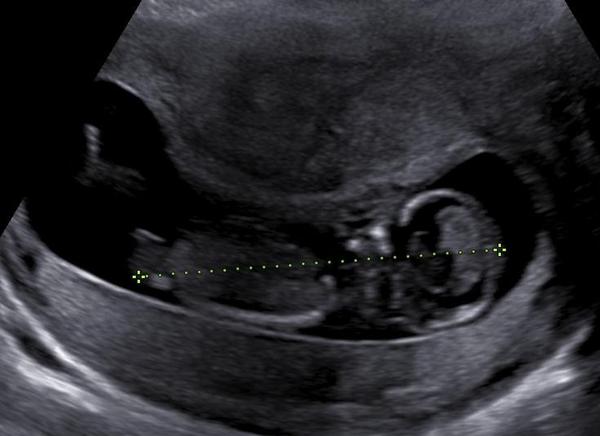

na screeningu ve 13. tt mi byl dělán UZ, při krerém byl bohužel přítomen velký akustický stín, zřejmě od myomu. Stín zcela znemožnil vyšetření celé břišní dutiny plodu, jakožto i bránice a vyšetření srdce dopplerem.

A má druhá otázka: Vím, že na tyto dotazy nerad odpovídáte a úplně chápu důvod, nicméně mi to nedá se nezeptat. Na jedné jediné foto z UZ je plod v celé délce poměrně hezky patrný a mně se zdá, že je i hezky vidět pohlavní hrbolek.

Mohu se zeptat na Váš názor, zda by se mohlo jednat spíše o holčičku?

Vím, že nic není jisté, jen mě zajímá, zda-li koukám správně.

A k té druhé časti dotazu: ano, fotografie velmi dobře zachycuje inkriminovanou oblast a opravdu se spíše jedná o holčičku. Nicméně, s nákupy a zařizováním pokojíčku vyčkejte na potvrzení v pozdějších fázích těhotenství po 20. týdnu. 🙂